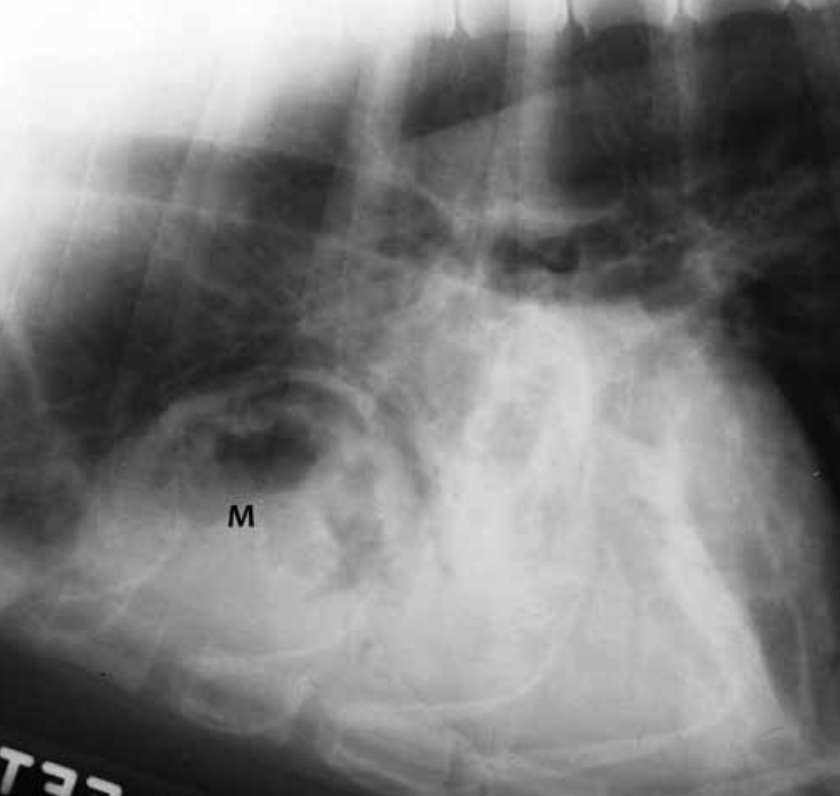

This is a typical appearance of what type of pulmonary lesion?

A

Abscess; thick wall with irregular inner luminal surface highlighted due to presence of central gas. Adjacent lobe affected by pneumonia.